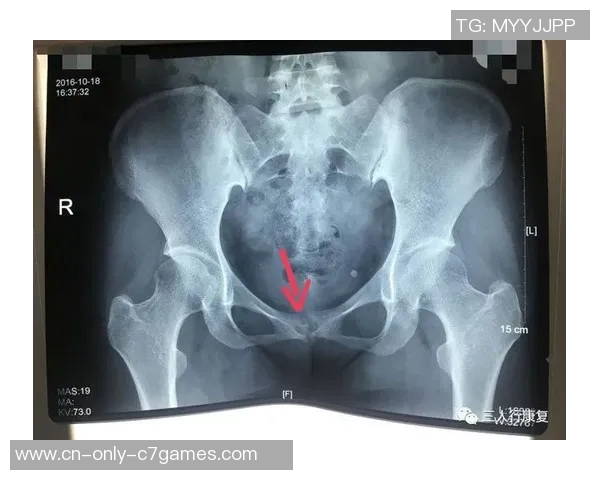

依据《米兰体育报》的报导,那不勒斯中场吉尔摩考虑手术医治耻骨炎,或许缺席至下一年一月。

本应由他担任洛博特卡的候补,而且也应该是安古伊萨的替代者。但是,吉尔摩正在考虑承受手术以彻底解决长时刻困扰他的耻骨炎问题,并已与沙龙达到共同。